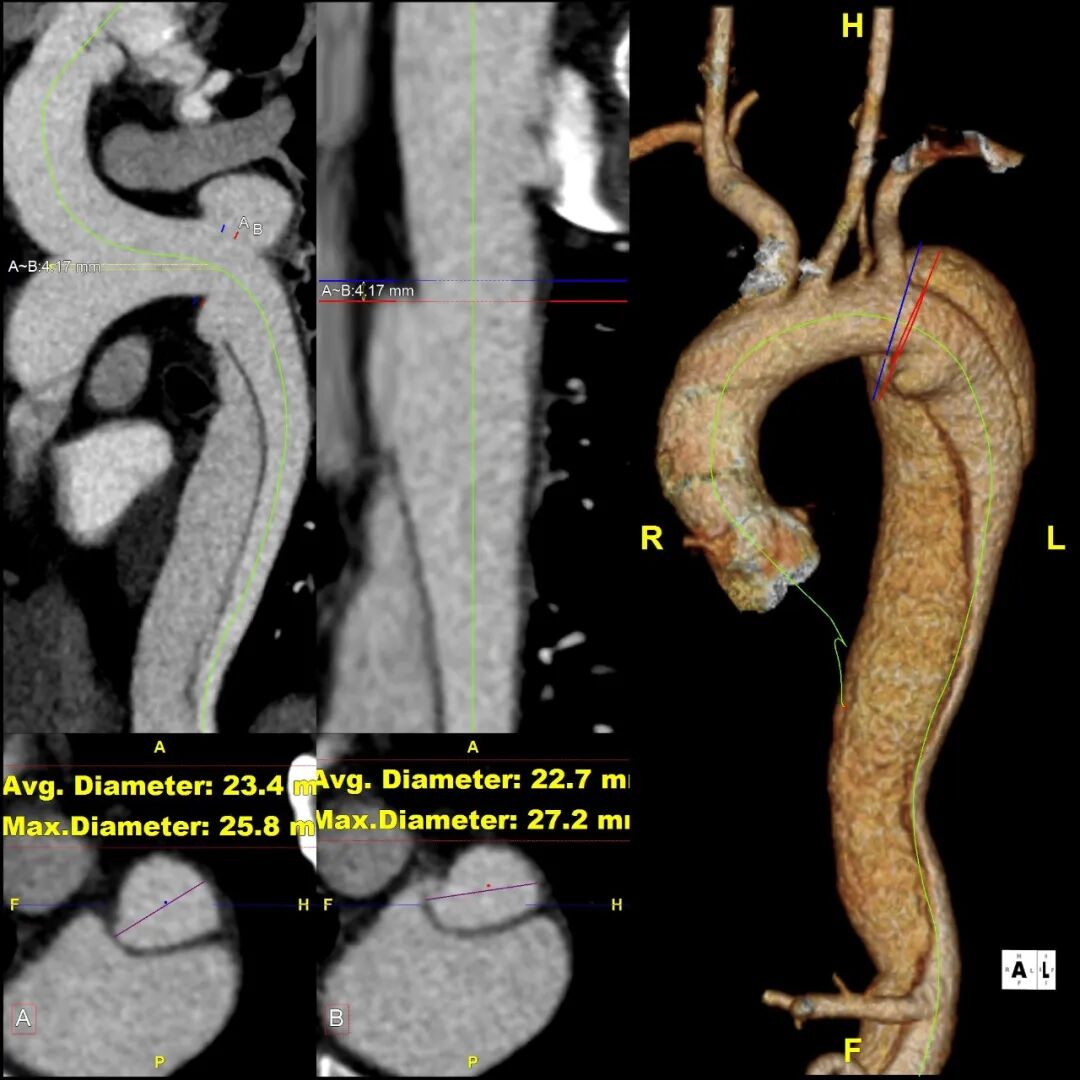

患者 10月前因“梗阻性黄疸、胆总管结石”检查发现主动脉夹层B型,否认腹痛、腰背痛,追问病史,2019年曾出现胸痛,行冠脉造影未见异常,当时血压170mmHg。诊断为:B型主动脉夹层累及到LSA后缘,左侧椎动脉发自于主动脉弓上的变异解剖形态

gore医疗怎么样「胸有乾坤」释半功倍 得心应手——GORE®TAG® 可主动调控胸主动脉覆膜支架治疗B型主动脉夹层病例分享 复旦大学附属中山医院_https://www.jmylbn.com_新闻资讯_第12张

gore医疗怎么样「胸有乾坤」释半功倍 得心应手——GORE®TAG® 可主动调控胸主动脉覆膜支架治疗B型主动脉夹层病例分享 复旦大学附属中山医院_https://www.jmylbn.com_新闻资讯_第13张

3.术前VS术后(3D影像)